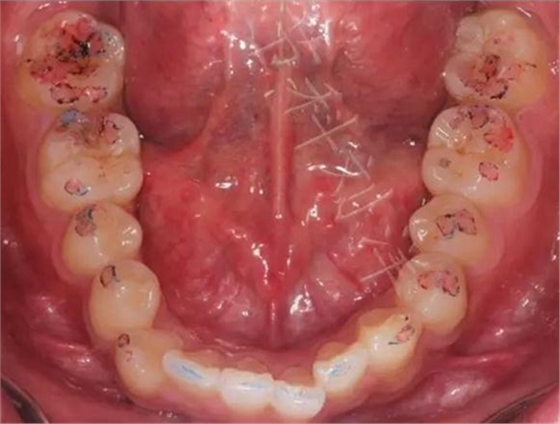

▲ 圖4:40μm咬合紙的效果

02,功能運(yùn)動(dòng)咬合點(diǎn)

①咬住200微米藍(lán)色咬合紙,前后左右磨,